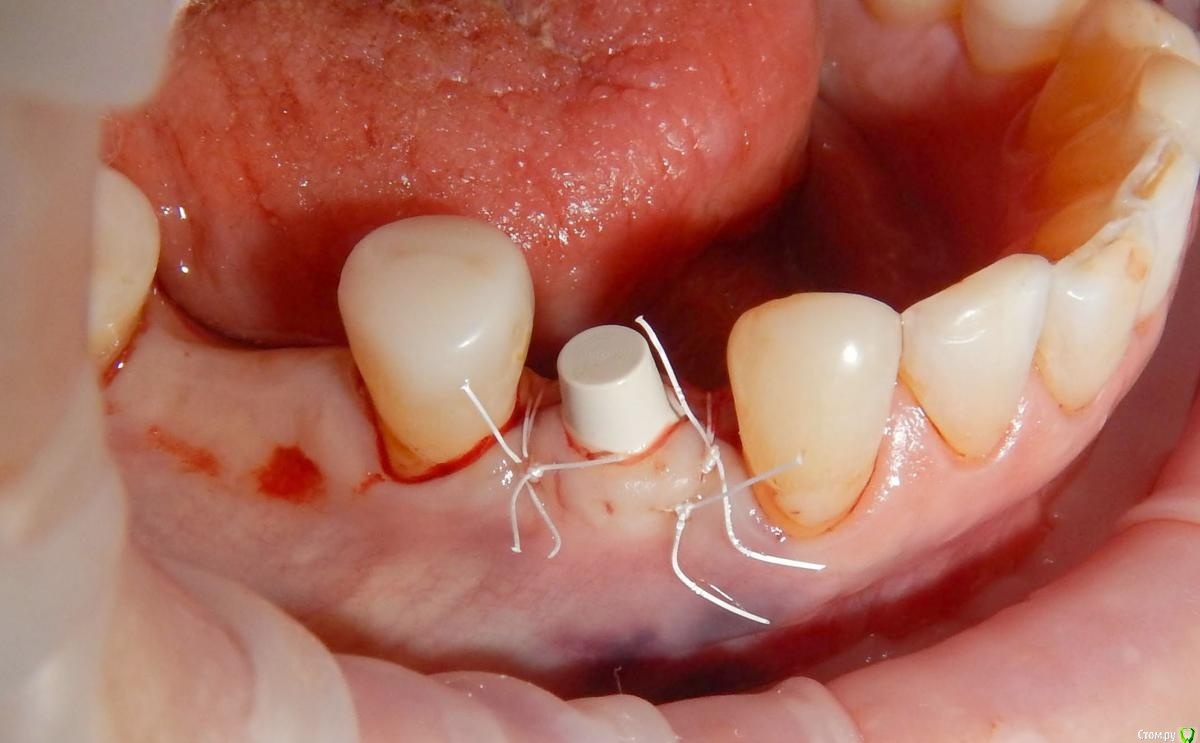

Astronaft Опубликовано 24 января, 2021 Поделиться Опубликовано 24 января, 2021 (изменено) Одиночный цирнокиевый имплантат и расщепление без графта. Пациентка:тонкая хрупкая женщина 55 лет, сконцентрированная на своем здоровье, в некоторой мере мнительная.всегда тяжелые заживления после удалений (по опросам)есть результаты Клиффорд теста (такая книжка под 200 страниц с in vitro аллерго-пробами на все известные материалы) Поставленная цель:только цирконий Мне было интересно найти вариант найболее приемленый пациентке и мне. С минимом хирургического риска и риском сожаления пациентки про выбор костного материала. Во-первых, я не использую аллографты - философски, чужие протеины, неприятный запах - просто основываясь на своем мнении.Во-вторых, мнительные пациенты склонны "пойти и почитать" до или потом и как следствие внушить себе вещи которых может и не было. Но по скольку мысль материальна... Все обсудил заранее.План: ридж сплит (расщепление), имплантат без графта, свободный СТ графт; если случается вестибулярная рецессия - пилим зирконий во рту. Ридж сплит сделан пьезотомом - крестальный и вертикальные пропилы на глубины около 8-10мм.Пилотное сверло.Развдвинул кость остеотомами от 1.6мм до 3.5мм в диаметре.Очень мягкая кость - напомнила мегкую максиллу плотности ногтевой пластинки вестибулярно.Имплант встал легко, но торк 40нсм. СТ графт из области 18. Деэпителизирую скальпелем уже потом. Тут интересно отметить, что я перестал боятся ошметков эпителия.Пончо сверху имплантата (а-ля шашлык Карлоса).Швы. PTFE всегда хорош. 12 недель.Красивая десна.Периотест -5.8 - отличный результат.Оттиск. Циркониевая коронка симметричная другой стороне. Изменено 24 января, 2021 пользователем Astronaft 19 Ссылка на комментарий

Astronaft Опубликовано 25 января, 2021 Автор Поделиться Опубликовано 25 января, 2021 Спасибо.День операции, 12 недель, день цементировки. 3 1 Ссылка на комментарий